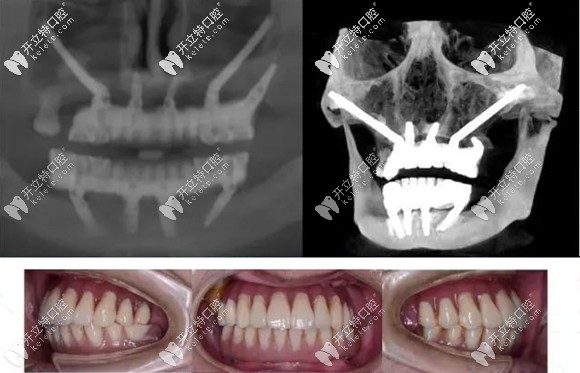

例如:術(shù)前采用專用軟件,結(jié)合患者口腔數(shù)據(jù),對(duì)種植方案進(jìn)行詳細(xì)手術(shù)設(shè)計(jì)。

采用3D打印患者上頜骨模型,在模型上先進(jìn)行摸擬手術(shù)。

制作手術(shù)導(dǎo)板,以便于在手術(shù)中進(jìn)行定點(diǎn)指導(dǎo)等措施。

做好術(shù)前準(zhǔn)備可避免穿顴穿翼種植并發(fā)癥的發(fā)生

正常情況,患者若身體條件許可,該種植技術(shù)是無(wú)需住院,無(wú)需全麻,也無(wú)需靜脈給藥鎮(zhèn)靜,在常規(guī)局部麻醉下就能進(jìn)行。

而且是局部小翻瓣,避免大翻瓣的創(chuàng)傷及術(shù)后較重的腫脹疼痛反應(yīng)。穿翼種植更是不翻瓣種植,術(shù)后即刻修復(fù),快速恢復(fù)咬合功能。

還可以消除對(duì)骨移植的需求,省去上頜竇提升手術(shù),縮短療程。

穿顴穿翼板種植牙技術(shù)以其卓越的效果贏得了廣泛的認(rèn)可,據(jù)相關(guān)文獻(xiàn)統(tǒng)計(jì),其10年以上的成功率可高達(dá)95%至97%,這無(wú)疑為眾多缺牙患者帶來(lái)了福音。在考慮此項(xiàng)技術(shù)時(shí),了解其潛在風(fēng)險(xiǎn)與顯著成效同樣重要,確保您做出最適合自己的選擇。